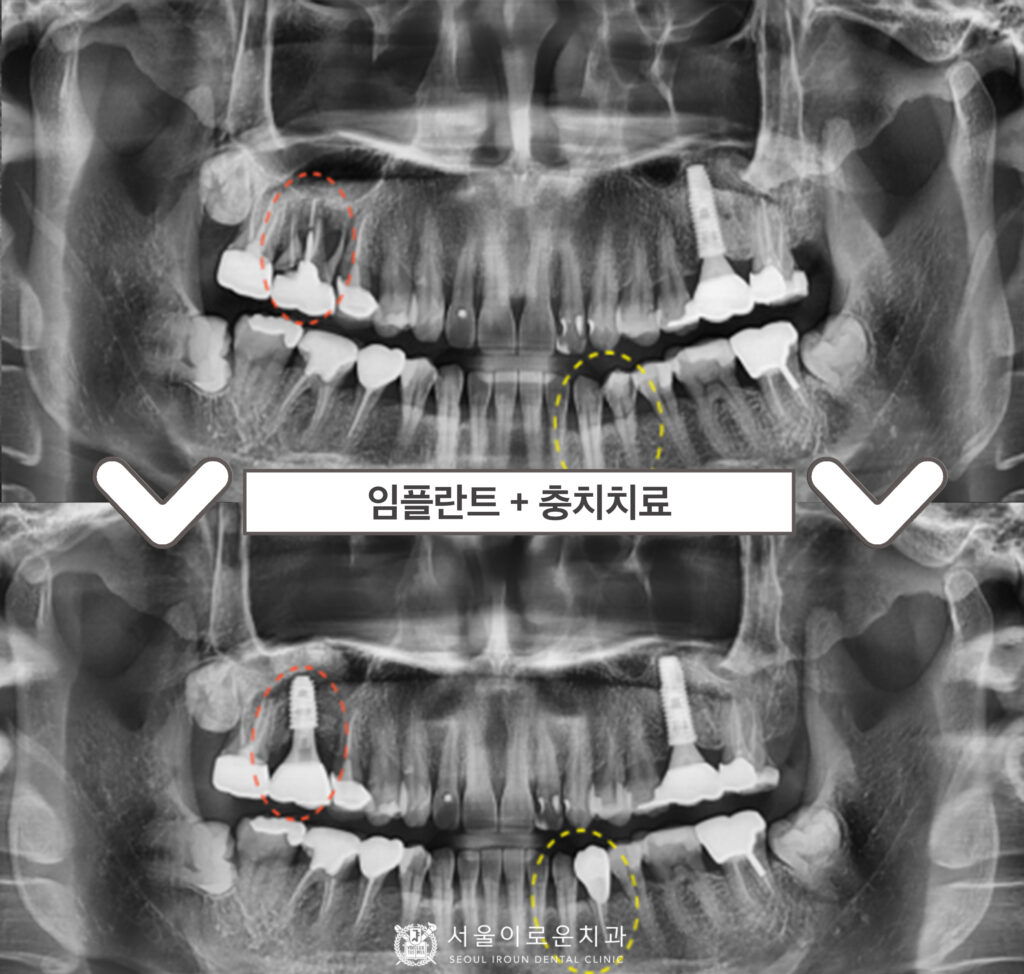

술 후 파노라마와 3D-CT를 통해

상악동 거상술을 동반한 임플란트가

안정적으로 식립된 것을

체크하였답니다.

더불어 오른쪽 임플란트 수술 후

픽스쳐가 잇몸뼈에

단단히 고정되기를 기다리는 동안

왼쪽 아래턱 치아 치료를 진행하였는데요.

송곳니(#33) 충치 제거 후 레진을

첫 번째 작은 어금니(#34)는

신경치료 후 크라운까지

깔끔하게 마무리해 드렸답니다.

서울이로운치과에서

모든 치료가 마무리 된 후

촬영한 파노라마 사진입니다.

임플란트 / 레진치료 /

신경치료 / 크라운치료를

모두 깔끔하게 잘 도와드렸답니다.

✅ 전 > 후 ✅

(2024.01.06ㅡ>2024.06.07)